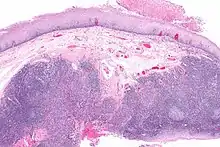

Diagnosis of oral cancer is completed for (1) initial diagnosis, (2) staging, and (3) treatment planning. A complete history, and clinical examination is first completed, then a wedge of tissue is cut from the suspicious lesion for tissue diagnosis. This might be done with scalpel biopsy, punch biopsy, fine or core needle biopsy. In this procedure, the surgeon cuts all, or a piece of the tissue, to have it examined under a microscope by a pathologist.[36] Brush biopsies are not considered accurate for the diagnosis of oral cancer.[37] Salivary biomarkers are also being under investigation with emerging outcomes and could potentially be used as a non-invasive diagnostic tool in the future.[38]

With the first biopsy, the pathologist will provide a tissue diagnosis (e.g. squamous cell carcinoma), and classify the cell structure. They may add additional information that can be used in staging, and treatment planning, such as the mitotic rate, the depth of invasion, and the HPV status of the tissue.